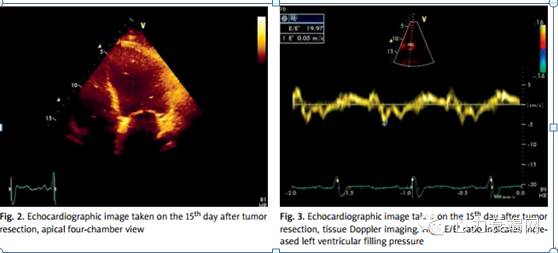

该患者是因运动耐力逐渐恶化症状,然后接受了心脏病诊断。随后即接受了外科治疗。手术切除了左室壁肿物(3*3cm)。术后由于发生了低心输出量(EF26%),需要使用儿茶酚胺,同时因缓慢性心律失常使用了临时心脏起搏器,使得在监护室内时间延长。术后15天(图2.3)患者转入心脏病医院。体格检查如下:血压 135/85mmHg,心率100次/分,双肺底啰音,下肢水肿。随后患者接受了心衰治疗。因既往有使用ACEi类药物引起的血管神经性水肿,故此次未给予该类药物治疗。超声随访EF值从26%上升至30%。药物治疗稳定了患者的症状。同时因患者已行根治性手术,故无需行放化疗。3月后超声示EF值提升至38%。12月后随访LVEF值40%,同时未见新发肿物。